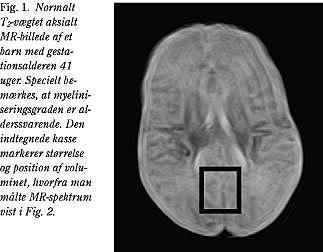

MR-scanning af hjernen fem døgn efter indlæggelsen viste normal MR-billeddannelse med T1 , T2 og diffusionsvægtede billeder (Fig. 1 ).